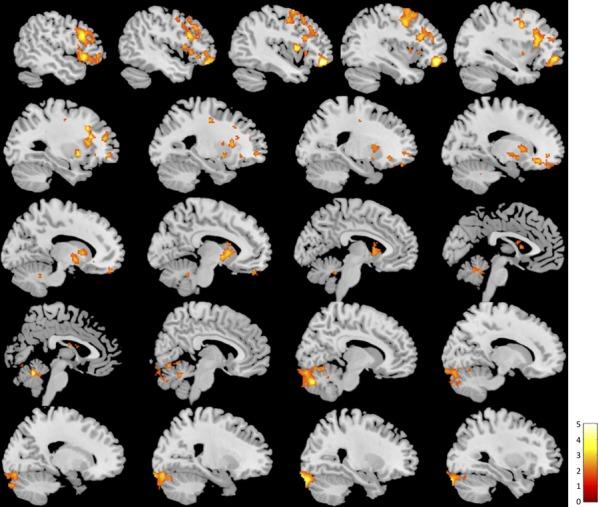

BOLD signal and functional connectivity associated with loving kindness meditation.

Loving kindness is a form of meditation involving directed well-wishing, typically supported by the silent repetition of phrases such as "may all beings be happy," to foster a feeling of selfless love. Here we used functional magnetic resonance imaging to assess the neural substrate of loving kindness meditation in experienced meditators and novices. We first assessed group differences in blood oxygen level-dependent (BOLD) signal during loving kindness meditation. We next used a relatively novel approach, the intrinsic connectivity distribution of functional connectivity, to identify regions that differ in intrinsic connectivity between groups, and then used a data-driven approach to seed-based connectivity analysis to identify which connections differ between groups. Our findings suggest group differences in brain regions involved in self-related processing and mind wandering, emotional processing, inner speech, and memory. Meditators showed overall reduced BOLD signal and intrinsic connectivity during loving kindness as compared to novices, more specifically in the posterior cingulate cortex/precuneus (PCC/PCu), a finding that is consistent with our prior work and other recent neuroimaging studies of meditation. Furthermore, meditators showed greater functional connectivity during loving kindness between the PCC/PCu and the left inferior frontal gyrus, whereas novices showed greater functional connectivity during loving kindness between the PCC/PCu and other cortical midline regions of the default mode network, the bilateral posterior insula lobe, and the bilateral parahippocampus/hippocampus. These novel findings suggest that loving kindness meditation involves a present-centered, selfless focus for meditators as compared to novices.